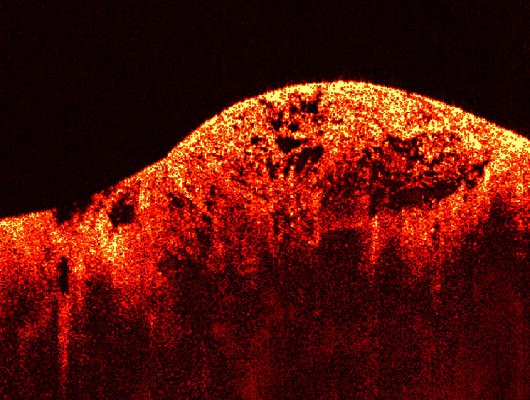

2. Leukemia

You may also know it as “Cancer of the Blood”, as it originates in the bone marrow, where blood is produced. The affected blood cells are your white blood cells, which are produced uncontrollably. There are 4 major types of leukemia:

Chronic leukemia: Begins as asymptomatic but worsens over time.

Acute leukemia: A rapid increase in the production of white blood cells.

Lymphoblastic leukemia: The leukemia affects the part of the marrow the produces lymphocytes – a type of white blood cells.

Myeloid leukemia: The leukemia affects the part of the marrow that produces red blood cells, as well as some minor white blood cells.

Prevention is managed by avoiding radiation sources, chemicals such as benzene, which is mostly produced by burning gasoline, as well as cigarette smoke.

Bone marrow sample of leukemia patient